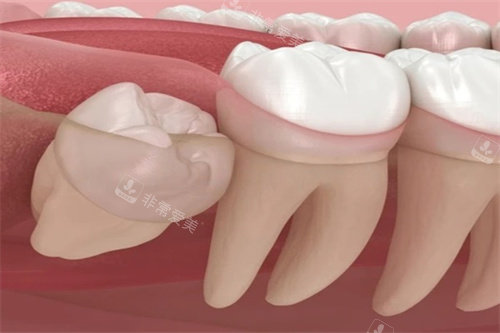

智齿,很多时候由于生长位置不正,容易引发智齿冠周炎等一系列问题,给患者带来疼痛和不便。

而残根则是牙齿因病或外伤等原因折断后残留的部分,不仅影响口腔卫生,还可能导致炎症。